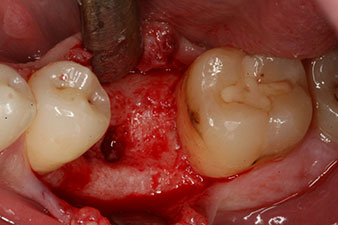

Fig. 3: After preparation with the Implantmed implantology motor, an implant (diameter 4 mm, length 12 mm) was screwed in by the motor at a torque of 43 Ncm.

The implant was placed as planned after thorough removal of the granulation tissue (blueSky, bredent).

peri-implant bone deficit

Fig. 5: The peri-implant bone deficit must be compensated with autogenous bone chips to restore the peri-implant tissue contour.

These values could have indicated open healing or even immediate restoration. Due to the insufficient crestal bone volume at the implant, the region was augmented with the bone chips collected during preparation of the implant bed and sutured to exclude saliva.